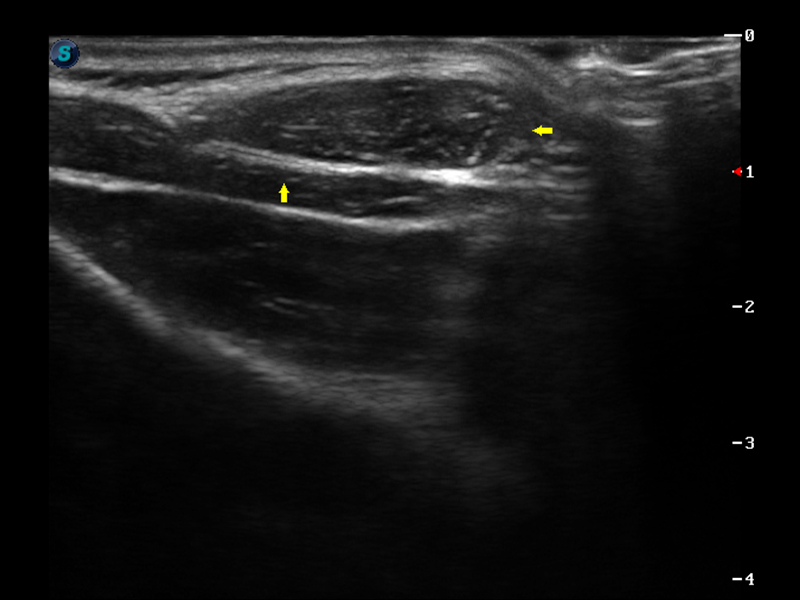

S9便携式彩色多普勒超声诊断仪是开立医疗研发的高端便携彩超设备,外观设计新颖、产品性能卓越。S9在便携超声领域采用了突破传统的触摸屏交互设计,并以先进的软件硬件技术和设计理念,为您带来清晰的图像质量、稳定的工作性能和便捷的操作体验。